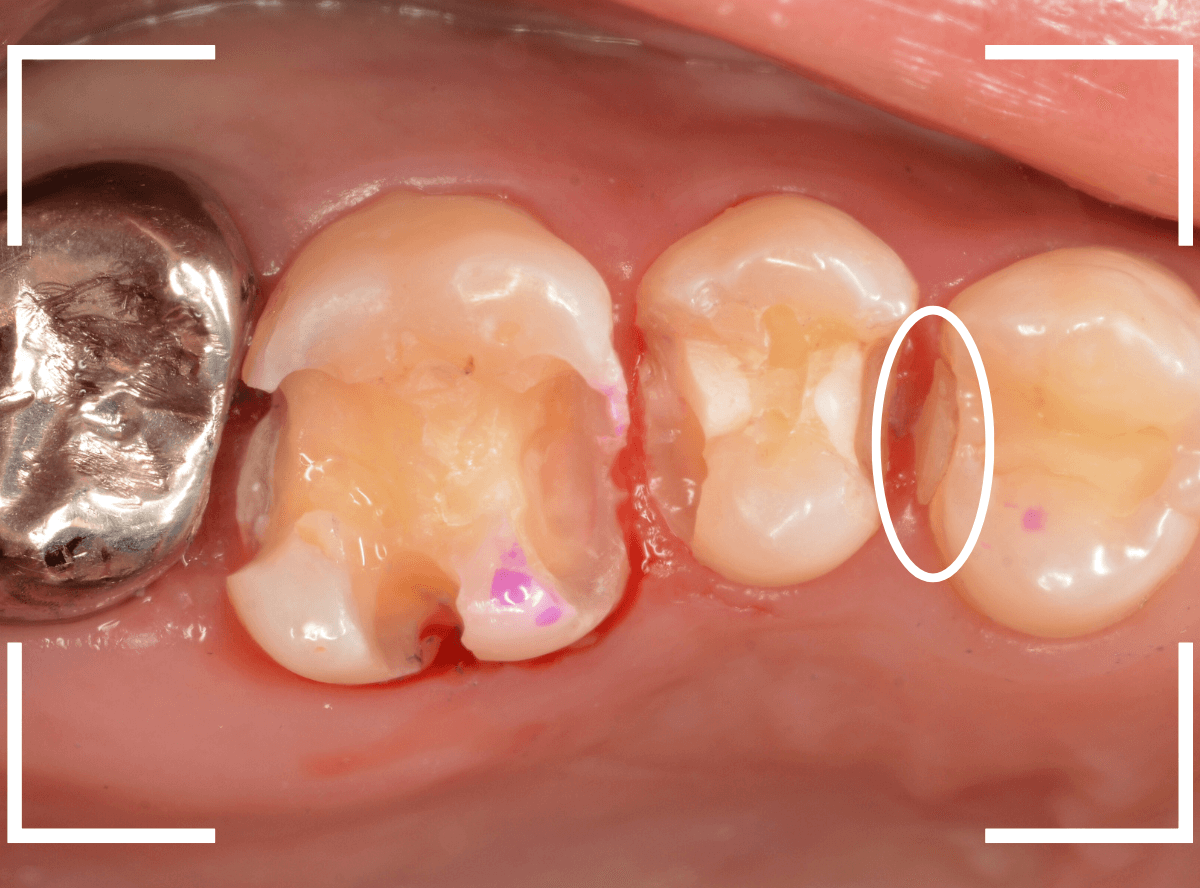

Case.10 レントゲンに写らない側面の虫歯を、少しずつ削って調べる

こちらも、虫歯が歯のあちこちで進行してしまっている患者さんのケースです。

特に側面の虫歯が深そうです。

側面にできた虫歯はレントゲン写真では診断しづらくやっかいです。

今回は「見るからに深そう」ですが。

さすがにレントゲン写真でも虫歯がありそうな事は確認できますが、実際にどうなってるのかはあまりはっきりわかりません。

少しずつ虫歯を除去していきます。

歯の側面から、手前の歯までつながった虫歯になっていました。

手前の歯までの虫歯を除去しました。

歯の後ろ側の側面も、大きな虫歯になっていますので、処置します。

隣の歯との間(隣接面)は、中で虫歯が広く進んでることが多いです。

結局、前後の歯に渡る広い虫歯でした。

レントゲン写真だけでは、ここまでの虫歯は判断できませんでした。